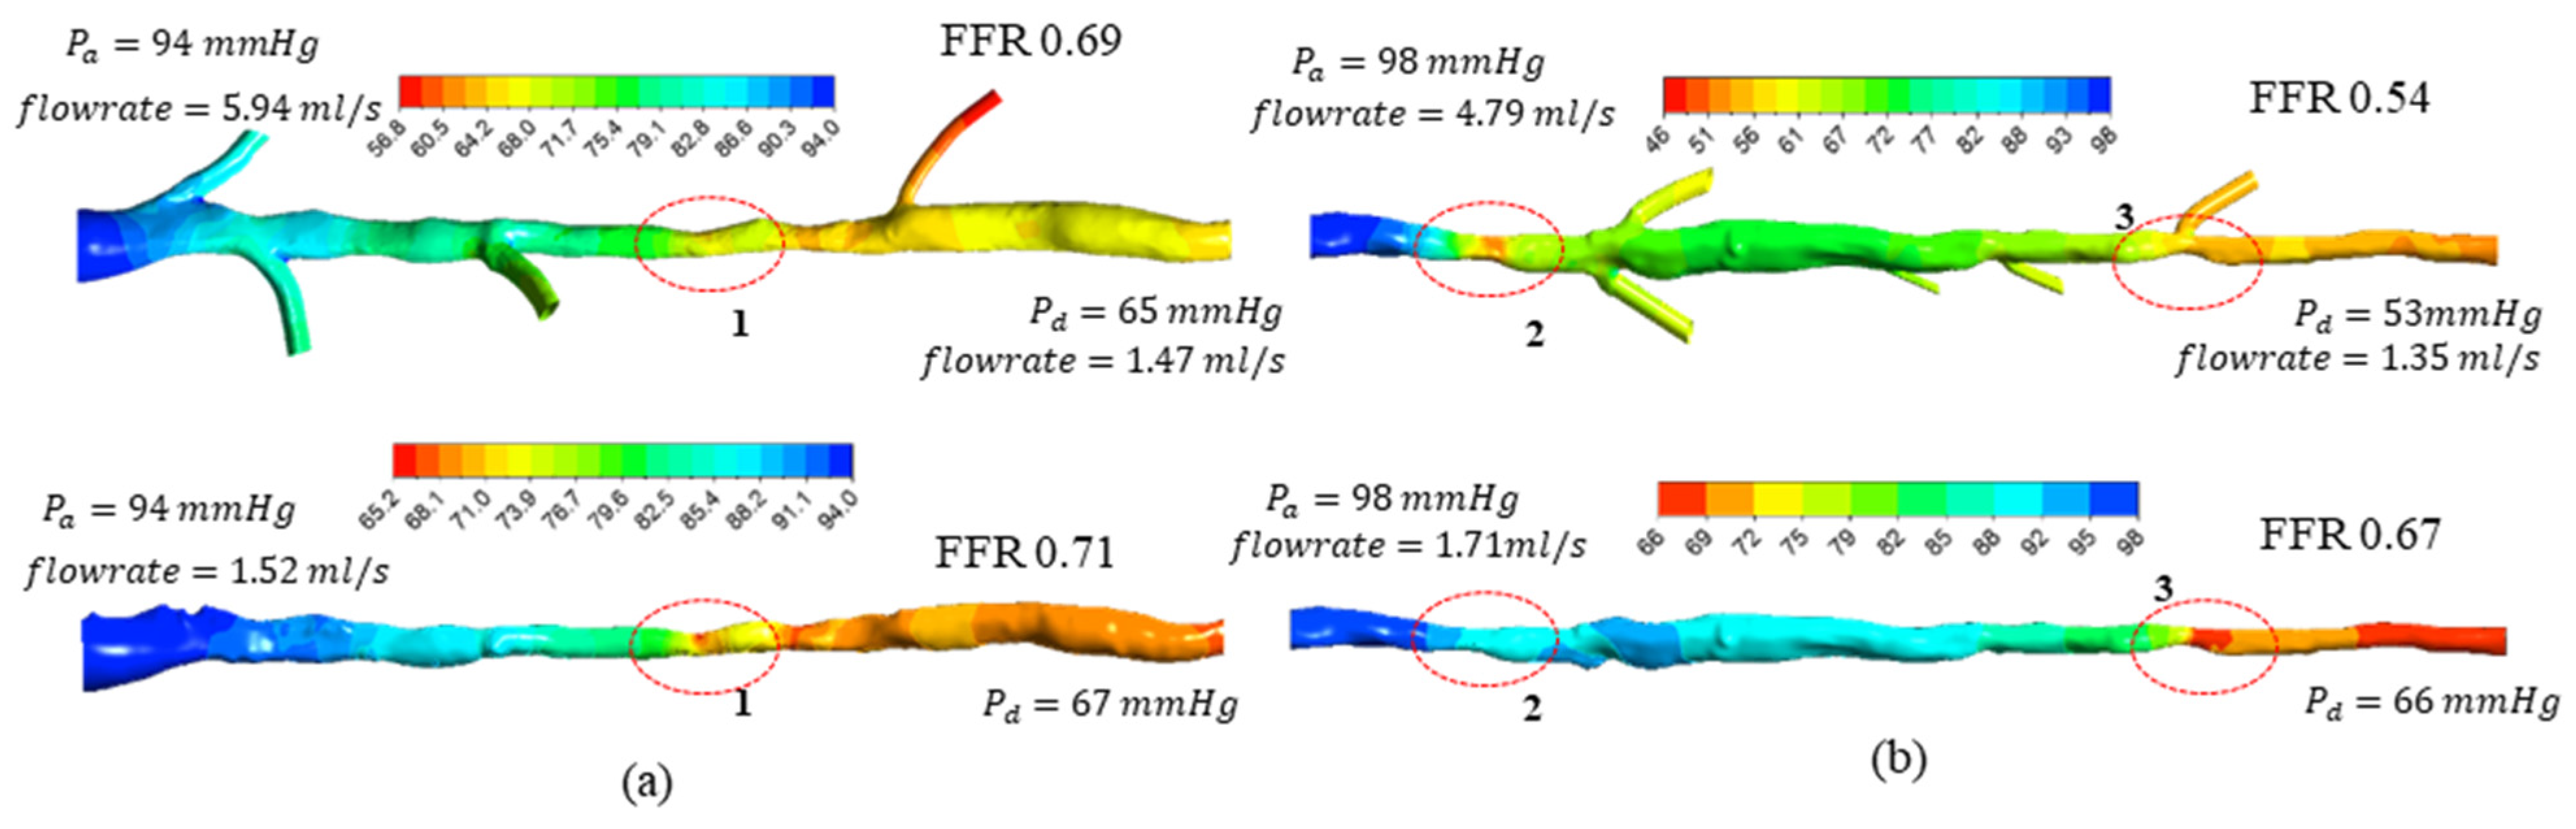

3.2. FFR Analysis in OCT-Reconstructed Vessel Models

3.3. Implications on FFR Computation Using OCT Imaging